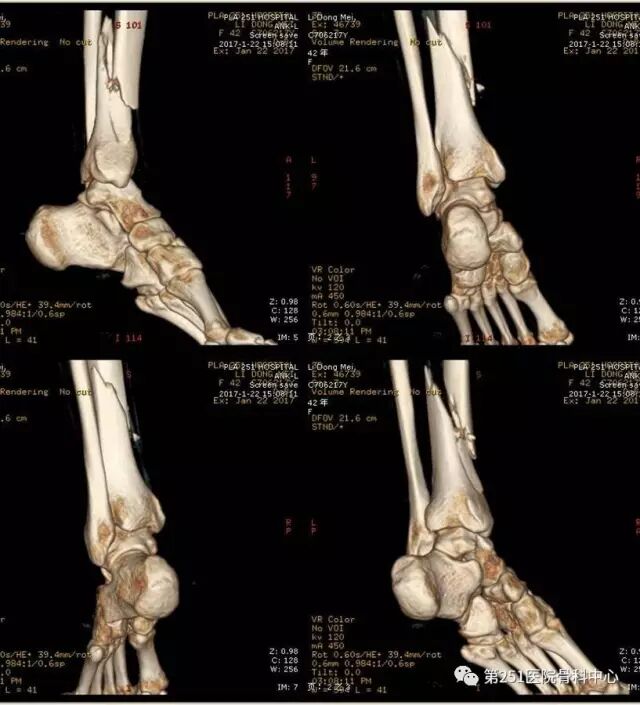

病例4:女性,车祸伤,同侧股骨、股骨颈合并胫腓骨骨折。

![]()